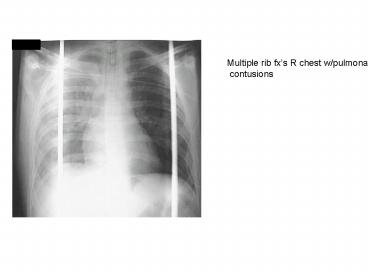

Multiple rib fxs R chest wpulmonary PowerPoint PPT Presentation

Title: Multiple rib fxs R chest wpulmonary

Multiple rib fxs R chest w/pulmonary contusions